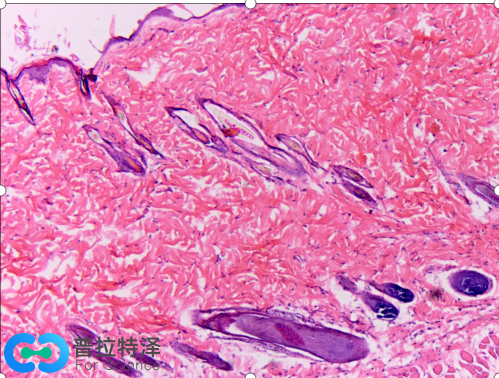

這是小鼠皮膚組織兩種病理染色圖片,左邊是馬松三色染色,右邊是HE染色。

右邊HE染色呈現(xiàn)藍(lán)色和紅色兩種顏色,而左邊馬松三色染色有灰黑色、紅色和藍(lán)色三種顏色,尤為明顯的是藍(lán)色。左圖中的大片藍(lán)色區(qū)域是皮膚上皮組織,結(jié)構(gòu)較為疏松,含有較多的膠原纖維,被馬松三色染色法中的甲基藍(lán)染成藍(lán)色。這樣染色后,可以清晰地看到毛孔在上皮結(jié)蹄組織中的分布。因此,被染成藍(lán)色的細(xì)胞外基質(zhì)(通常都含有膠原纖維)就能和細(xì)胞以及其他組織形成鮮明的對比,從而易于觀察。在某些病理狀態(tài),如心肌梗死,肝硬化和腎纖維化等情況下,病變的細(xì)胞會被結(jié)締組織取代,用馬松染色能很好地發(fā)現(xiàn)病變部位,并能對病變進(jìn)行定量的評估。因此,直到今天,馬松染色依然是組織學(xué)和病理學(xué)中活躍的染色方法,并出現(xiàn)了幾種改良的馬松染色,使得染色效果更加理想。

Masson染色預(yù)期結(jié)果:膠原纖維、粘液、軟骨呈藍(lán)色(如光綠液染色為綠色),胞漿、肌肉、纖維素、神經(jīng)膠質(zhì)呈紅色,核黑藍(lán)色。